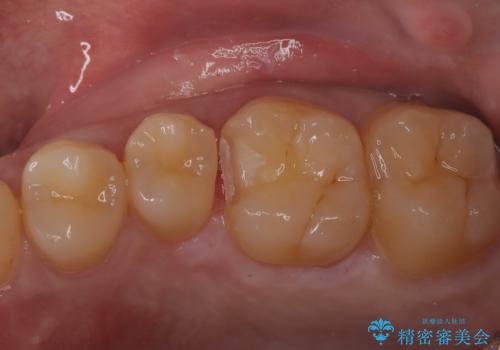

虫歯の再発リスクを減らすセラミックインレー

- 他院でインビザラインの治療中に虫歯を発見されたため、治療を希望され来院された患者様です。

セラミックインレーにて治療を行いました。

セラミックインレーは適合が良く、虫歯の再発リスクを減らすことができます。